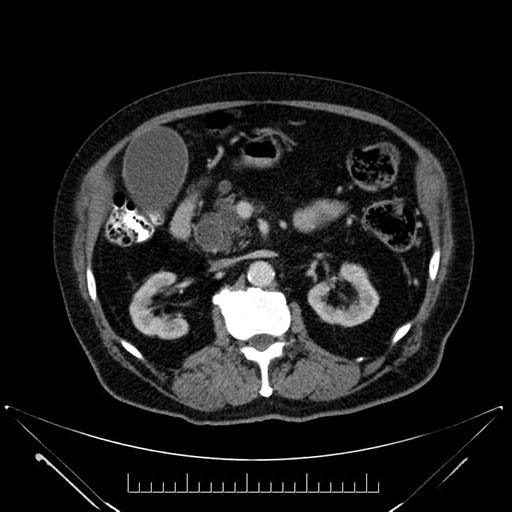

Coronal - stented